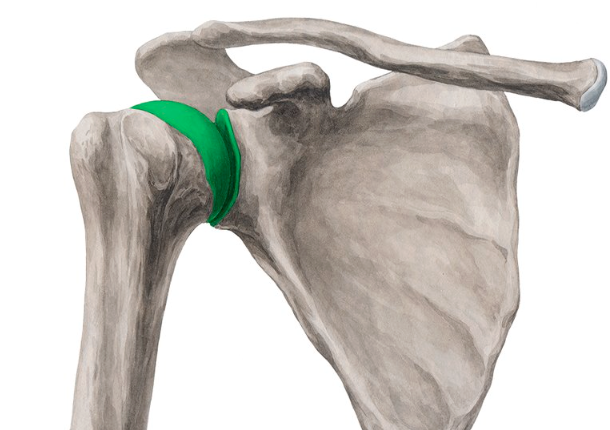

what is the highlighted joint?

glenohumeral

what kind of joint is the glenohumeral joint?

synovial, ball-and-socket